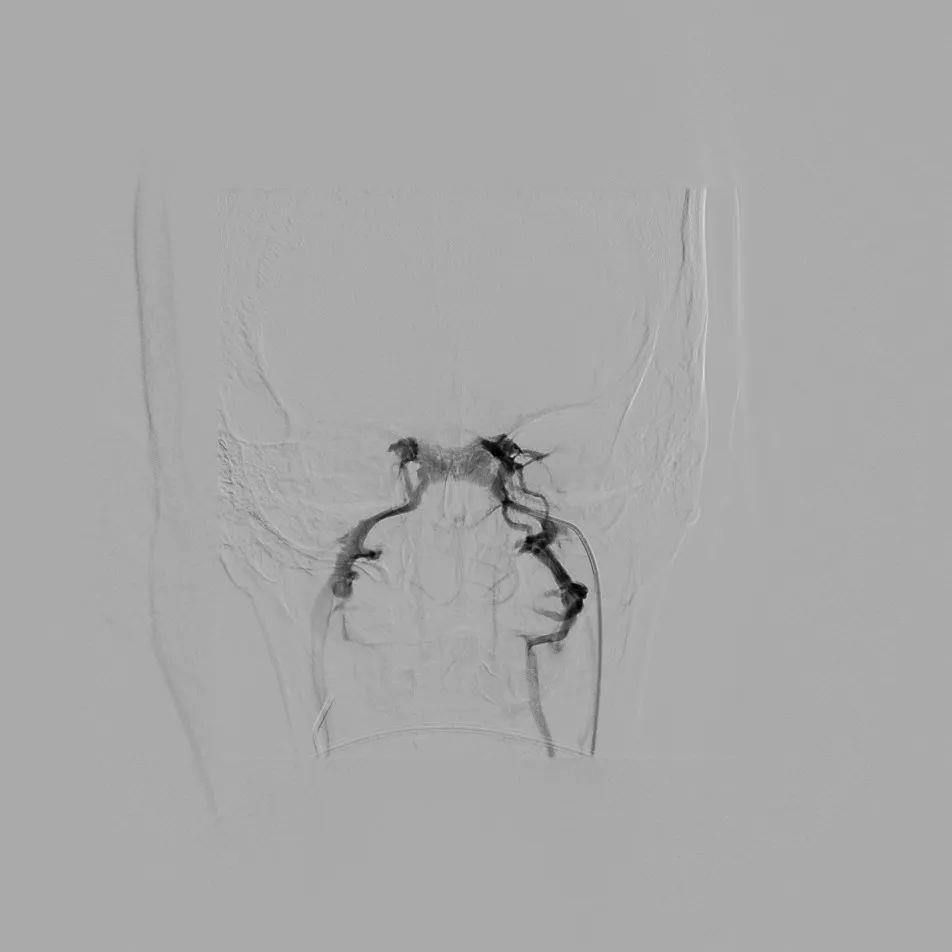

术中插管于双侧岩下窦静脉造影明确并采血

经微创介入团队实施岩下窦静脉采血术,采血结果经过检验提示为岩下窦静脉ACTH含量明显高于外周静脉血含量,明确为中枢性来源,遂转入神经外科行垂体瘤切除术。术后患者恢复良好,激素水平及皮质醇节律均恢复正常。